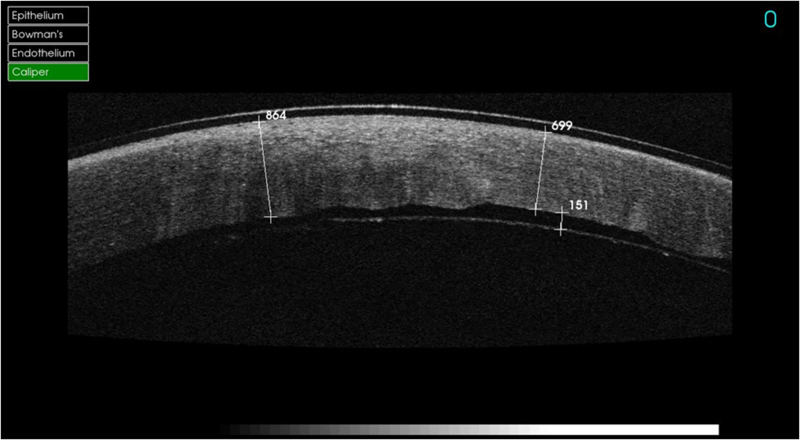

Podemos mostrar unos ejemplos para ver la utilidad de la OCT. En los casos de opacidades anteriores que no afectan al endotelio se realiza la técnica de DALK. La mayoría de pacientes están afectados por opacidades estromales infecciosas, como el virus del herpes simple (VHS), por distrofias corneales, y también por el queratocono. En la

Figura 6 podemos observar una técnica de DALK predescemética, en este caso observamos un lecho de estroma, MD y endotelio de 42 micras. Ésta técnica es de elección en casos donde se quiere evitar realizar una cirugía penetrante por los riesgos que comporta (por ejemplo el herpes corneal). En la siguiente foto podemos ver una DALK descemética realizada en una paciente con queratocono (

Figura 6. DALK predescemética.